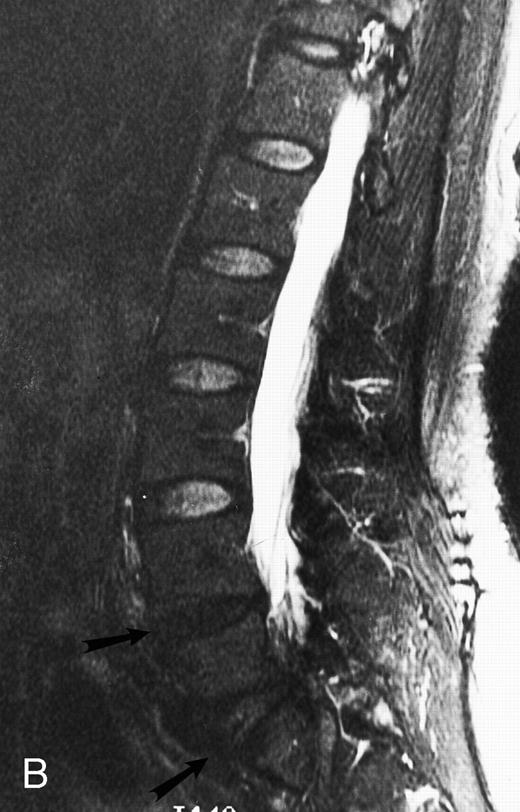

Normal appearance of spinal bone marrow in a 45-year-old woman: T1-weighted (500/11, TR/TE) (A) and T2-weighted, fat-suppressed fast spin echo (4000/96, TR/TE, ET 16) (B) sagittal MR images of the lumbar spine. Note increased signal of the vertebral bodies, relative to the intervertebral discs in (A) and increased deposition of fatty marrow around the basivertebral veins (arrowheads). On the T2-weighted image, normal intervertebral discs are brighter than the vertebral bodies; low signal in the L4-L5 and L5-S1 discs is due to degenerative changes (arrows).